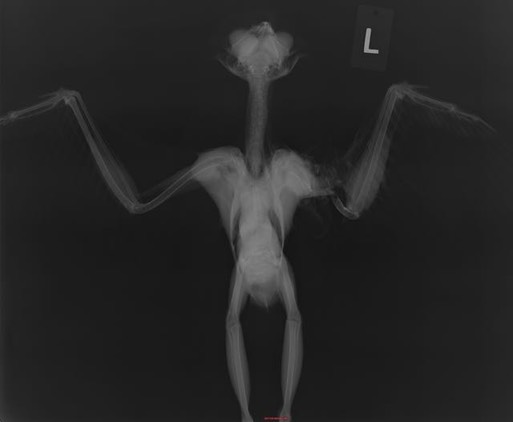

Two Great Horned Owls and a Sharp-shinned Hawk also had injuries too extensive to repair. The Great Horned Owl below had a humerus fracture that was totally unrelated to the air rifle pellet near her backbone. She was shot at a minimum of several months ago. The wound had completely healed. She was in excellent condition until a collision of some type (perhaps with a car or power line) resulted in her broken wing.